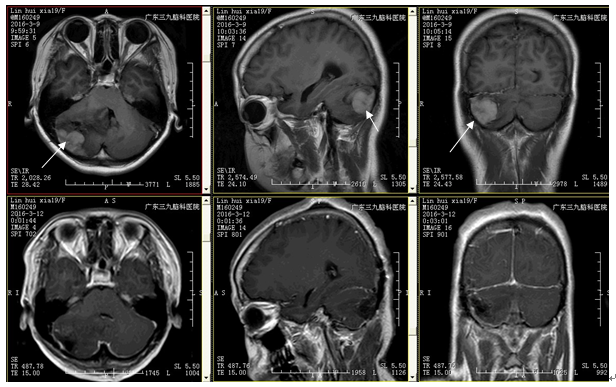

患者林某某,女,19岁,因头痛1月于2016年03月入院。入院时神志清楚,正确对答以及遵嘱活动,双侧瞳孔等大等圆,对光反射灵敏,四肢肌力5级,肌张力正常,生理反射存在,病理征阴性。辅助检查:外院头颅CT示:颅内占位性病变,未见片及报告。

治疗:入院后完善相关检验检查及术前准备,在全麻下行右侧小脑肿瘤切除术,术中可见肿瘤位于右侧小脑,血供丰富,边界欠清楚,质韧,肿瘤深面可见坏死组织,镜下予全切除肿瘤,术程顺利,术后予脱水、改善脑功能、预防感染、止血、对症、支持等综合治疗。术后复查头颅CT、MRI示:呈术后改变,肿瘤全切除。术后病理:髓母细胞瘤(WHO IV级)。

诊断:髓母细胞瘤(右侧小脑,WHO IV级)